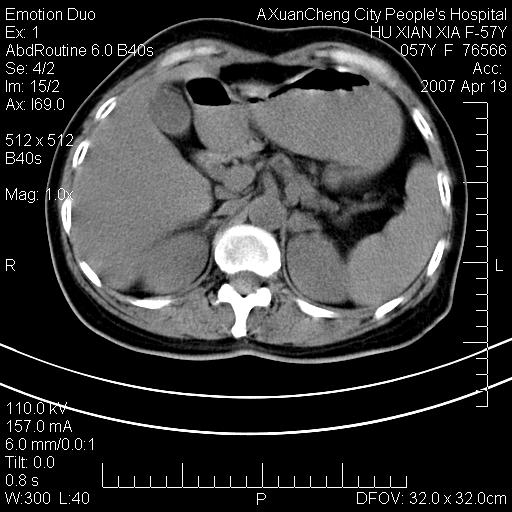

考虑:1、双侧肾上腺占位.2、肝左叶内侧段不规则低密度灶,建议强化扫描.

双侧肾上腺增大,有分叶,密度均匀,考虑转移建议查原发灶

1.双侧肾上腺占位,转移首先考虑。